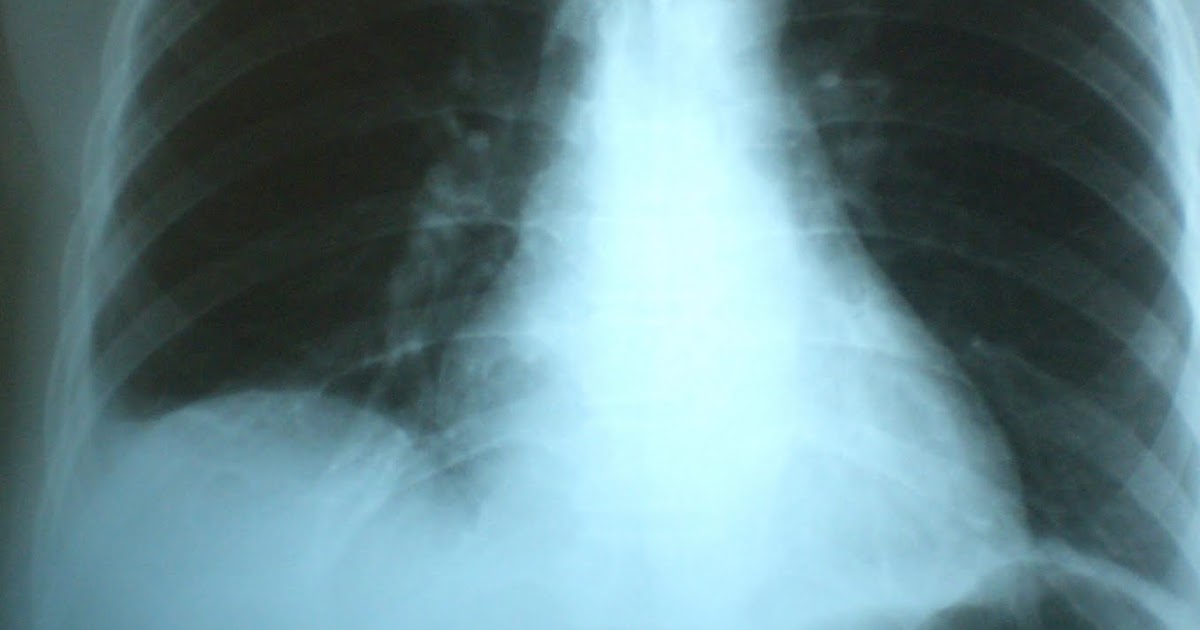

What Is Plate Like Atelectasis . Note the bilateral basal plate like atelectasis. Atelectases) refers to the collapse or incomplete expansion of pulmonary parenchyma. This is a lung collapse that takes a linear shape. It's one of the most common breathing complications after. It often happens when the airway is blocked. Atelectasis means a collapse of the whole lung or an area of the lung. We present a case with convex platelike atelectasis at lower lung zone that looks very similar to free air under right hemidiaphragm. It is very difficult to differential diagnosis from hollow organ perforation that need emergency surgical management. Atelectasis may be used synonymously with collapse,. Plate like atelectasis (sub segmental atelectasis) is an example of focal loss of surfactant. Pneumothorax is a condition where air leaks into the space. Atelectasis is a condition where alveoli in your lung or a part of your lung deflates, causing a partial or complete collapsed lung.